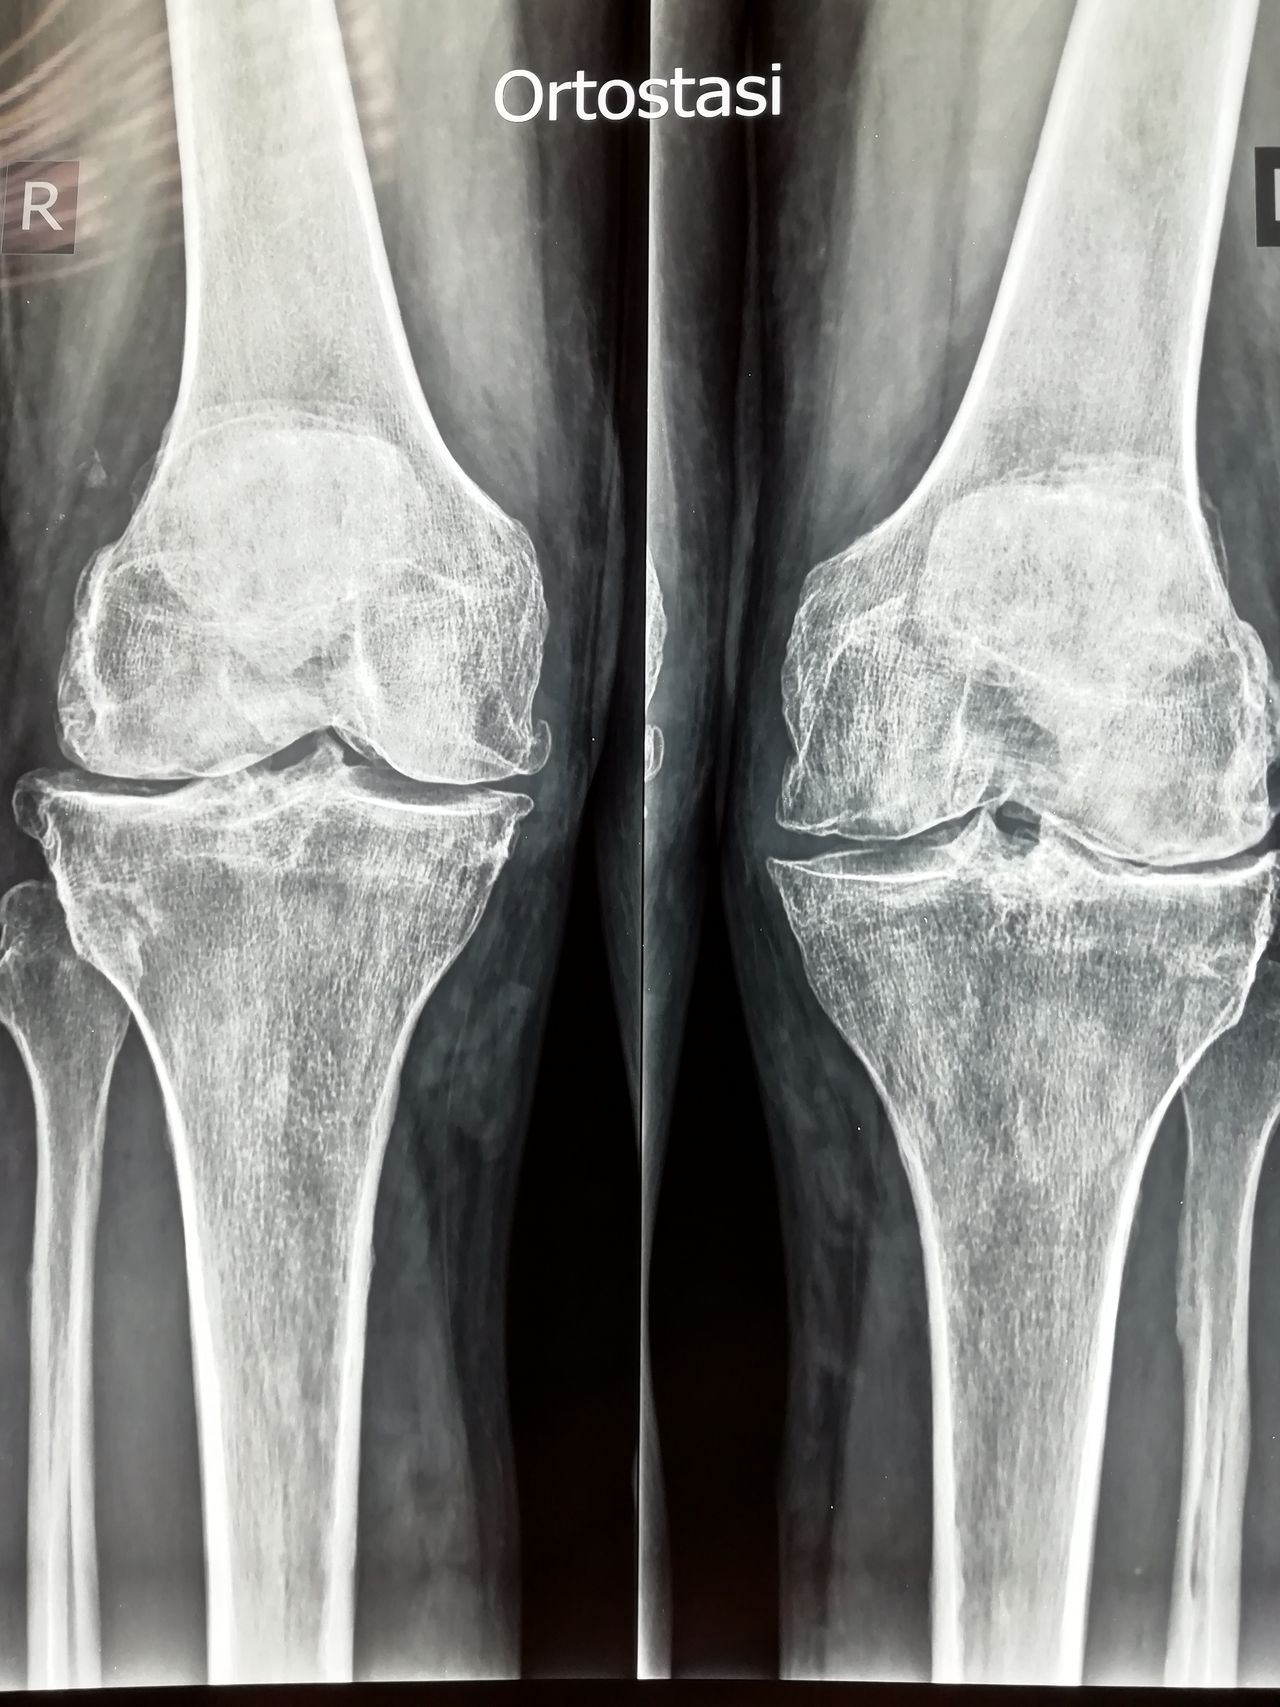

Salve buona sera gentili spettabili dottori l'anno scorso mi trovavo al pronto soccorso scrivo da Sanremo Liguria e dopo lastre e venuto fuori che avevo una frattura al coccige a novembre del anno scorso . Ma in sentivo dolori e la cosa strana e che io non ero caduta una caduta lebbi 5 anni fa dalle scale ma era risultato che avevo solo le costole rotte e niente altro ma già dal 2019 dopo la caduta cominciai a soffrire di solito di schiena forti a ogni sforzo di servizio fisico lavorativo e questi dolori si accentuavano di più anche una settimana arriva del ciclo e anche durante il ciclo Poi mi avevano fatto pure una lastra alla schiena ed era venuto fuori una discopatia alla schiena ma non si sa di che tipo di discopatia. Ora però l'anno scorso era un anno più o meno che non avevo più dolori forti ma erano diminuiti alla schiena in questi ultimi mesi di quest'anno sarà per errore che non avendo cose morbide per potermi sedere soprattutto quando vado in bagno perché non lavora attualmente per altri problemi di salute. E non ho entrate economiche. Ma fatto sta che adesso sarà un mese che ho di nuovo il coccige che mi fa male che non riesco a sedermi e la schiena è aumentato il dolore a cui ho difficoltà ad abbassarmi a sedermi e anche per dormire chiedo consigli cosa mi conviene fare per potermi riprendere e che attività potrai ancora svolgere in questo stato anche se poi ho anche problemi alla schiena discopatia e anche al ginocchio gonartrosi bilaterale infiammazzione e riduzione cartilagine del ginocchio sinistro Ringrazio cordialmente i spettabili dottore attendo un vostro riscontro buona sera.

gentile signora . di solito succede che il corpo, a seguito di cadute, corregge il tiro con accomodamenti posturali. nel tempo pero' arriva sempre il conguaglio di tutto cio' che abbiamo accumulato come patologie. lei è stata specifica e meriterebbe una risposta specifica, ma bisogna fare i conti con la realtà. dovrebbe andare da un collega il quale sarebbe in grado di aiutarla ma se no puo' si accontenti di piccoli accorgimenti. tutta la colonna è un sistema e adesso il sistema è in tilt. bisogna che lei si metta in posizione supina con le gambe flesse e fare delle respirazioni diaframmatiche se il dolore è urente, muovere entrambi le gambe flesse a destra e sinistra completamente per muovere il bacino e sacro. mettersi un lato , e anche dall'altro successivamente, in modo comodo tale da mettere un arto dritto e l'altro, non a contatto con il letto o lettino , allungato . compiere respirazioni e sentire dove fa male e aspettare il rilassamento. di piu' al momento non posso dirle. appena puo' vada da un Osteopata e quando si siede metta una ciambella.